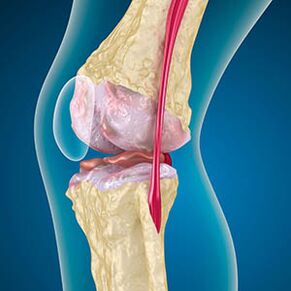

Esant artrozei kremzlė, išklota kaulų kraštais dilimu arba visiškai nėra. Pažeistas audinys nėra skausmo šaltinis, nes jame nėra receptorių. Netoliese esančių struktūrų uždegimas sukelia būdingus simptomus.

Kūnas tęsia pažeistų audinių regeneraciją, tačiau kremzlė auga netolygiai. Dėl to susidaro nelygumai, kurie sužeidžia kitus sąnario elementus. Osteofitų pobūdis paaiškinamas kompensacija už sklandų sąnario kremzlę. Kita versija rodo, kad „Spurs“ augimas Dėl raumenų susilpnėjimo jis susijęs su bandymu stabilizuoti sąnario medialinį ar šoninį.